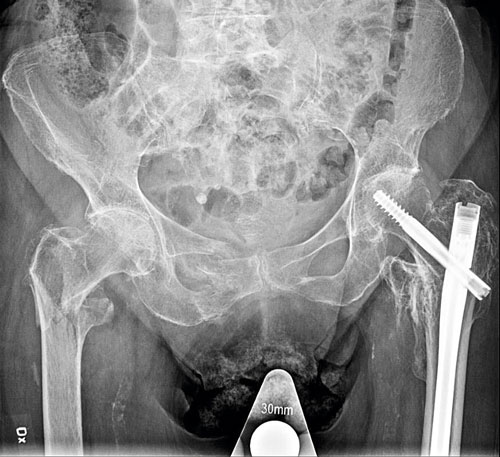

Patienter som drabbats av höftfraktur har förhöjd risk för ytterligare osteoporosfrakturer. Patienten på bilden hade tidigare opererats på grund av vänstersidig pertrokantär fraktur med märgspik och var nu aktuell med en liknande högersidig fraktur. Patienten hade även färska högersidiga ramusfrakturer.